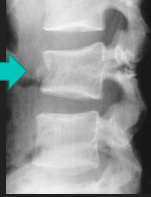

Spondylolisthesis

Forward movement of one vertebra in relation to another.

Spondylolisthesis commonly occurs due to a developmental defect in the ____, spondylolysis, or severe osteoarthritis.

Pars Interarticularis

Spondylolysis

Stress fx through the pars interarticularis of the lumbar vertebrae